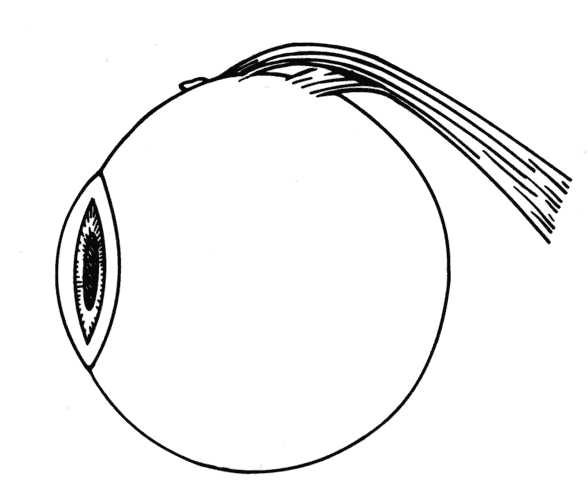

In some situations, a portion of a horizontal rectus may be left at the insertion site (Figs. 9 and 10). The muscle is usually split at the time of the initial procedure, and this can cause a shift of the distribution of force at the insertion and cause vertical misalignment. The pattern of the strabismus and the details of the previous surgery should provide clues to the problem and allow a logical approach for correcting the vertical deviation. Suspicions should be confirmed by careful dissection and exploration of the region of the muscle insertion. The importance of careful evaluation and elimination of mechanical restrictions cannot be overemphasized.4,10

Fig. 9. Residual exotropia or hypertropia can occur if a portion of the lateral rectus muscle is not recessed with the first procedure. To prevent this, care must be taken to incorporate all portions of the tendon when recessing an extraocular muscle.

Fig. 10. The pole test, or sweeping a Stevens muscle hook anterior to the insertion, will ensure that the entire tendon is on the Jameson muscle hook.